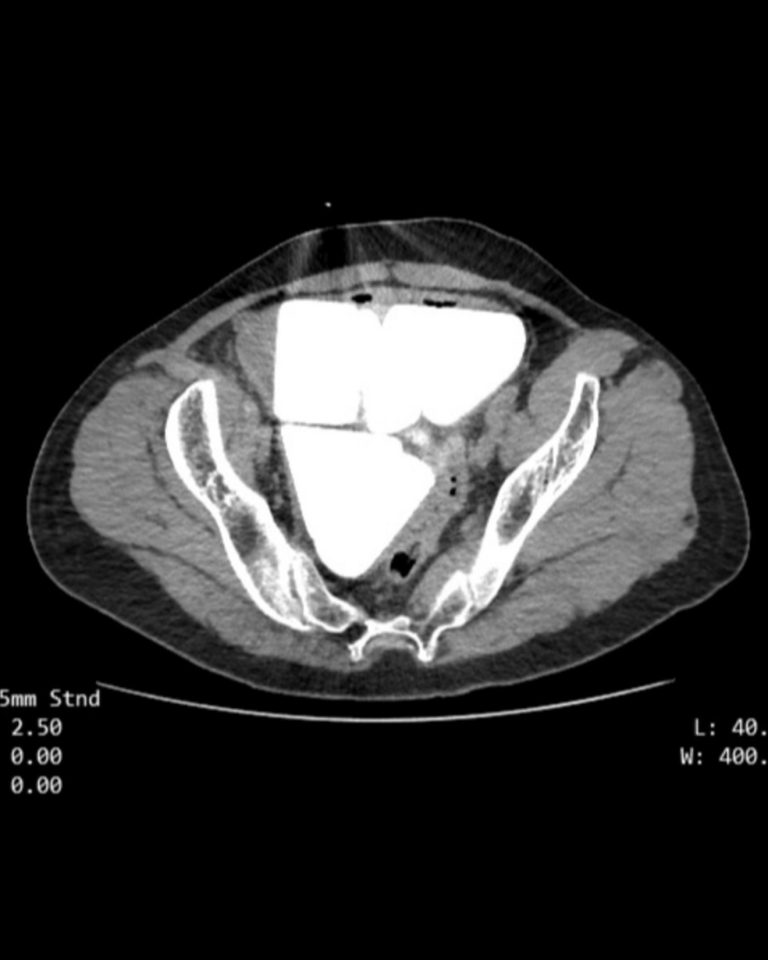

Обстеження показало дивні утворення у сечовому міхурі чоловіка (фото: needtoknow.co.uk)

Виявилося, що в сечовому міхурі чоловіка були розташовані гігантські камені у рівних геометричних пропорціях. З шести конкрементів один мав форму куба, а п'ять — у формі рівносторонньої піраміди.

Чоловіка негайно поклали в лікарню, а згодом провели успішну операцію. Під час втручання хірурги виявили, що довжина сторони кубічного каменю має довжину у 7 см з усіх сторін, а ребра піраміди були завдовжки 6 см, а загальна маса каміння склала понад 2 кг.